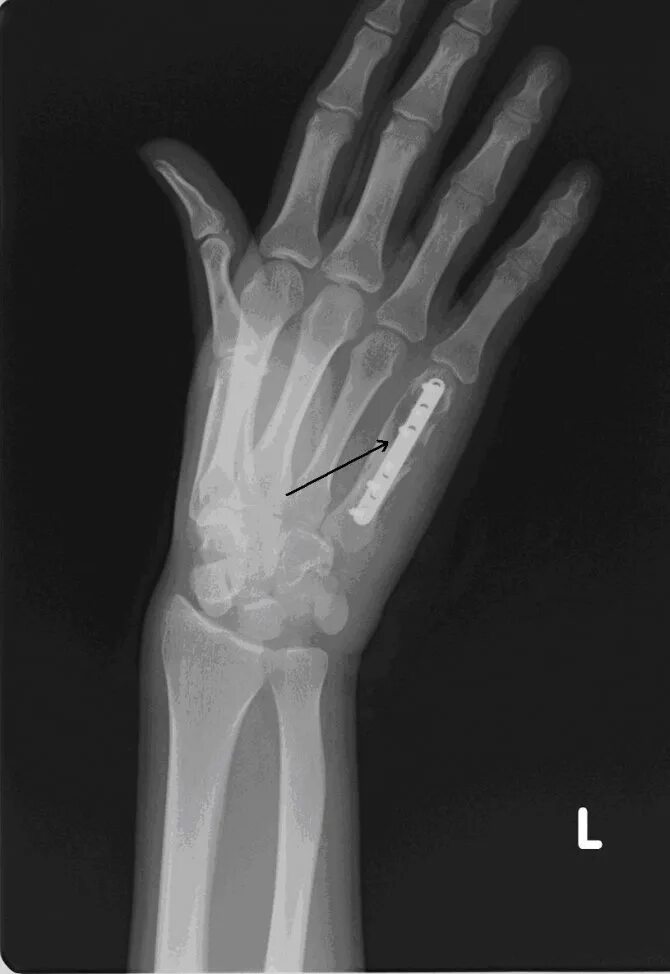

Перелом 3 пястной кости